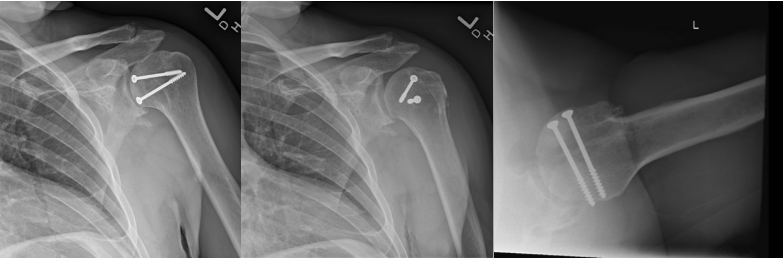

The reverse Hill-Sachs defect involved approximately 40 percent of the articular surface, with nonviable cartilage at the base of the defect. The glenoid cartilage and remaining posterior humeral head cartilage were intact. A humeral head osteochondral allograft was contoured to match the wedge-shaped defect and provisionally stabilized with Kirschner wires. Definitive fixation was achieved with two countersunk 4.0-mm cancellous screws (20 mm and 45 mm) (Figures 2 and 3).

After fixation, the construct was stable throughout range of motion, restoring articular congruity. The subscapularis and rotator interval were repaired, and the patient was placed into a gunslinger shoulder immobilizer postoperatively.